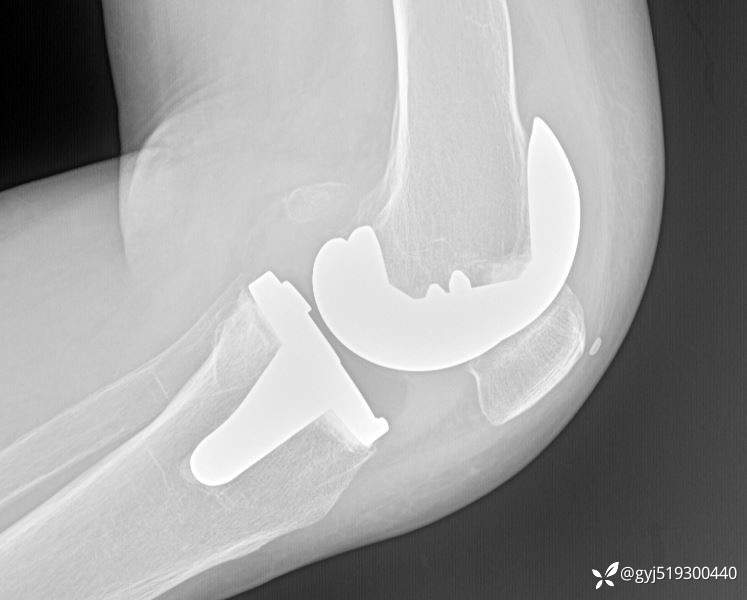

患者女性,68岁,两年多前行左侧膝关节置换,术后断断续续疼痛,期间膝关节肿痛明显,外院抽液化验后考虑滑膜炎。既往无高血压,糖尿病,类风湿等

本次入院后,见膝关节肿胀明显,皮温稍高,外侧间隙压痛,活动度因肿胀轻度受限,检查炎性指标均正常。予以膝关节穿刺抽液,抽出50ML血性液。